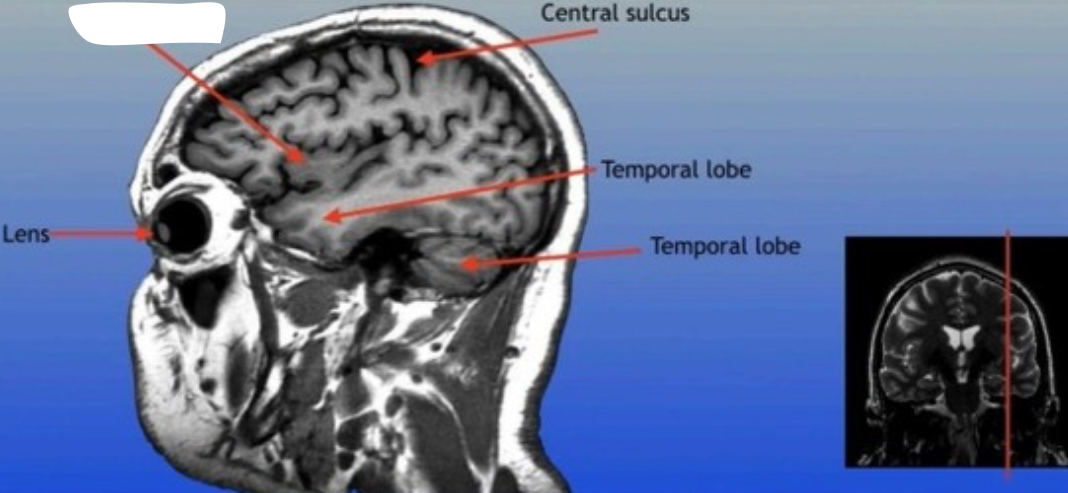

Central Sulcus

A prominent groove in the brain that separates the frontal lobe from the parietal lobe, important for distinguishing motor and sensory functions.

Frontal Sinus

A paired cavity located within the frontal bone, above the eyes, that plays a role in sinus drainage and resonance of the voice.

Optic Nerve

The bundle of nerve fibers that transmits visual information from the retina to the brain. It plays a crucial role in the sense of sight.